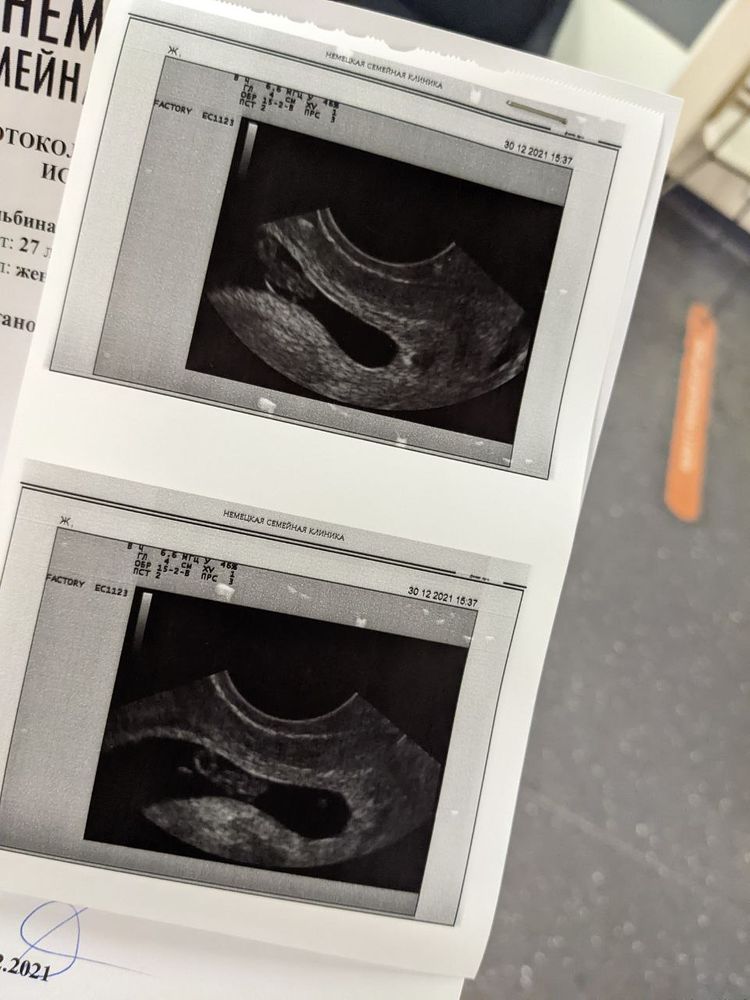

Всем привет. У меня первое узи. 21дпп 3х дневочки. ПЯ в полости матки. 10.8мм ЖМ + . Сколько он не написали.Просто сказала, что есть. Но ПЯ продолговатое, мне ношпу добавили и все. Утром на туалетной бумаге , прожилки крови были, но Ре посмотрела сказала чисто. У кого было ПЯ не идеально круглое, опасно ли это? Переживаний теперь еще больше.

Добрый день! У меня вот такое было, даже не сказали ничего про это. На первом фото без мбриончика, на втором уже с ним